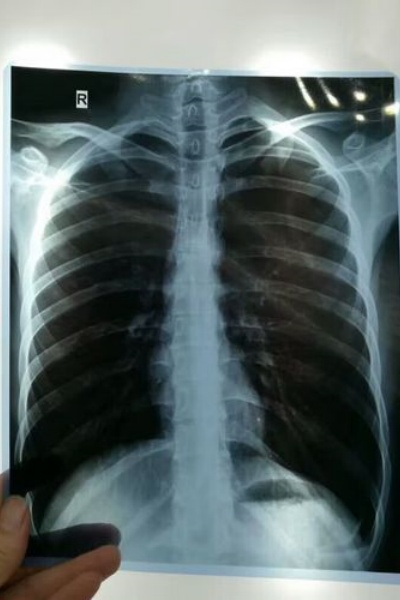

在没有智能手机没有电脑的时代,放射诊断技术的全部家当,就是一张张单薄的胶片,医生们把它们夹在观片灯上,像观赏一幅幅油画,在强光下寻找疾病。黑白片影像,裹藏着身体隐秘,医生们用眼睛和经验,一次次寻找反常的蛛丝马迹。

但胶片是个“小公主”,娇贵得不得了,不能弯折、不能潮湿,否则影像不清晰,诊断不准确。胶片的保存问题,医院里得留出一个大房间,把胶片摞得整整齐齐,一排排“影像小山”,时间长了,要找一张特殊胶片,如同大海捞针,急得医护人员团团转。

进入21世纪,全数字化的潮流到来。DR(数字X光摄影)系统全面上线了,不用一个胶片跳板直接就将x光信号转化为数字图像,速度很快,检查完医生就直接能在电脑里看到图像了。